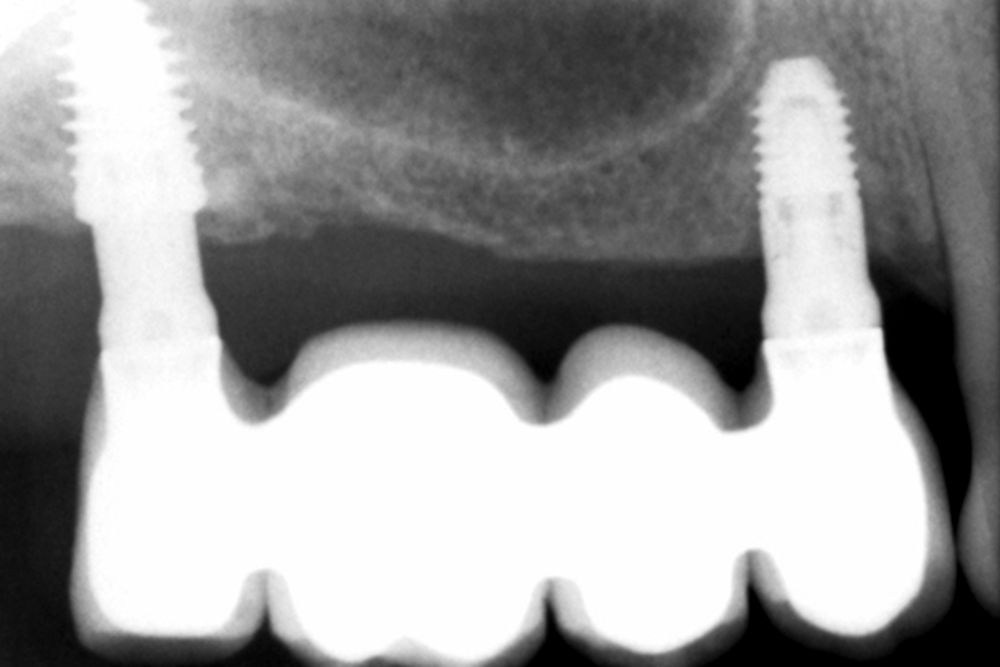

Como primer paso, se realiza un escaneado intraoral de la paciente, para poder generar un encerado virtual con las piezas que queremos rehabilitar con implantes (Figuras 6-8). Esto nos permite planificar con claridad el caso y desde el modelo tridimensional, generar los provisionales y las guías quirúrgicas basadas en la posición protésica, que desde el flujo digital pueden imprimirse (Figuras 9-14). Desde el encerado podemos además generar otras guías, en este caso radiológicas, con las que realizar el Cone-Beam Computed Tomography (CBCT) de planificación. Con esta información tenemos en el mismo estudio radiológico la fusión de nuestra planificación quirúrgica y la posición real de la prótesis adaptada a la oclusión, muy útil para generar una planificación que contempla todos los parámetros. En este caso, se planifican implantes cortos de 6,5 mm en el primer cuadrante, de morfología Core-Xâ, para lograr una correcta estabilidad primaria en un tipo óseo IV como vemos en el corte seccional (Figuras 15 y 16). En el segundo cuadrante, con similares características, planificamos implantes de 6,5 y 5,5 mm de longitud (Figuras 17 y 18).

El fresado de este tipo de implantes, al basarse en la oseodensificación en toda la longitud, se realiza a menor diámetro, en dos tramos, uno para el cuerpo del implante y otro para el ápice, que siempre tiene una mayor capacidad de penetración y menor diámetro. Para una situación de hueso tipo IV/V en el maxilar , fresaremos hasta 2,8 mm en la zona del cuerpo y a longitud de 1,8 mm para el ápice, lo que se corresponde con la fresa piloto. Con ello al insertar el implante generamos una compresión lateral que produce una mayor estabilidad primaria en estas zonas de baja densidad (Figuras 19 y 20). Una vez colocado el implante, todo el hueso que le rodea, circunferencialmente alcanza una mayor densidad, lo que produce que la estabilización sea mayor en toda su superficie (Figuras 21 y 22). Si realizamos una comparativa entre el volumen condensado mediante la colocación de un implante convencional y uno de la morfología Core-Xâ, se observa la diferencia entre el cuerpo del implante y el fresado, lo que nos da una idea de la diferencia en la consecución de la estabilidad primaria (Figuras 23 y 24).